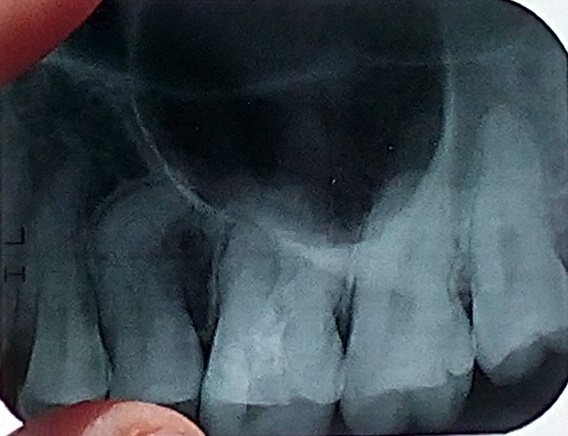

Установлена киста шестого зуба. Указанный зуб пломбировался два года назад.

Подскажите, пожалуйста, можно ли утверждать, что причиной образования кисты стало направильное лечение? Будет ли результат от лечения лазером? И что посоветовали бы вы в данном случае? К/Т зуба:

Причина очевидна, некачественное лечение каналов, да его в принципе нет. Конечно причина кисты именно в этом.